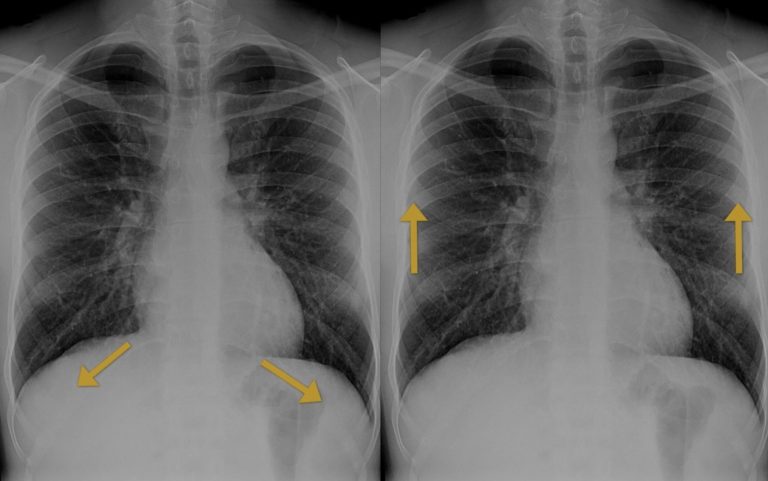

When a patient is upright, intrapleural gas will rise to the top, which is why pneumothoraces are usually detected here.

The two cardinal signs to look for are, firstly, a lucent black area of lung without visible vascular markings and, secondly, a thin white pleural line representing the visceral pleura separating from the parietal pleura. Compare side to side: if one apex lacks markings where the other has them, this should ring alarm bells. Bullae from emphysema can mimic a lucent pneumothorax, but these tend to be round and do not display a sharp pleural line paralleling the chest wall.

Here in this case we have the two cardinal signs of pneumothorax: one, a white pleural line (yellow arrow) and two lucency without lung markings outside of this.

In supine ITU patients, pneumothoraces may not rise to the apex and instead present as the ‘deep sulcus sign’ with an abnormally lucent and deepened costophrenic angle.